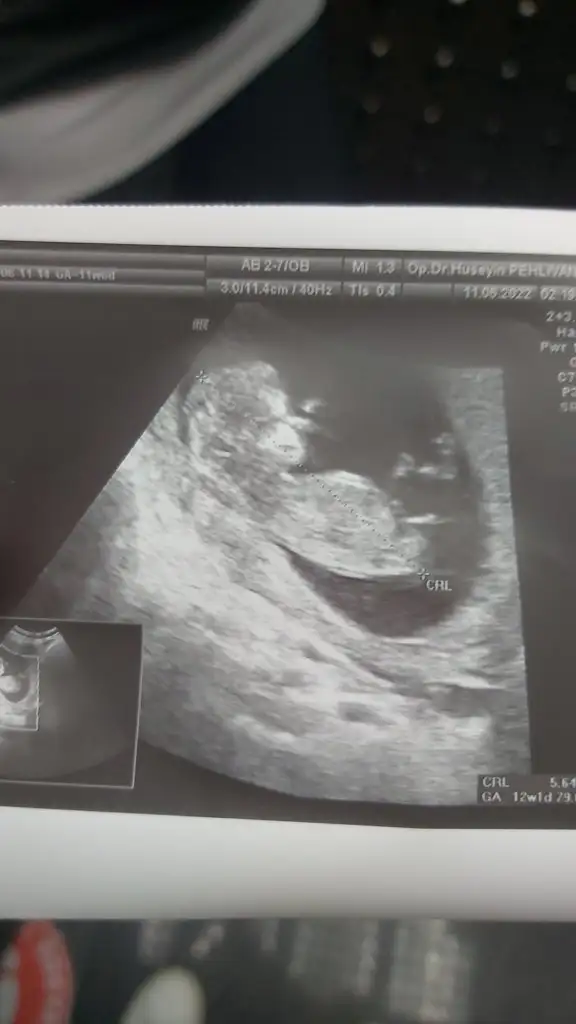

paşa gibiPasha22 teyzemiz 10+1 günlük karından ultrason bize de tahmin de bulunur musun

teoriye göre erkek ama bence prenses8+1 vajinal ultrason yorum yaparsanız sevinirim teşekkür ederim